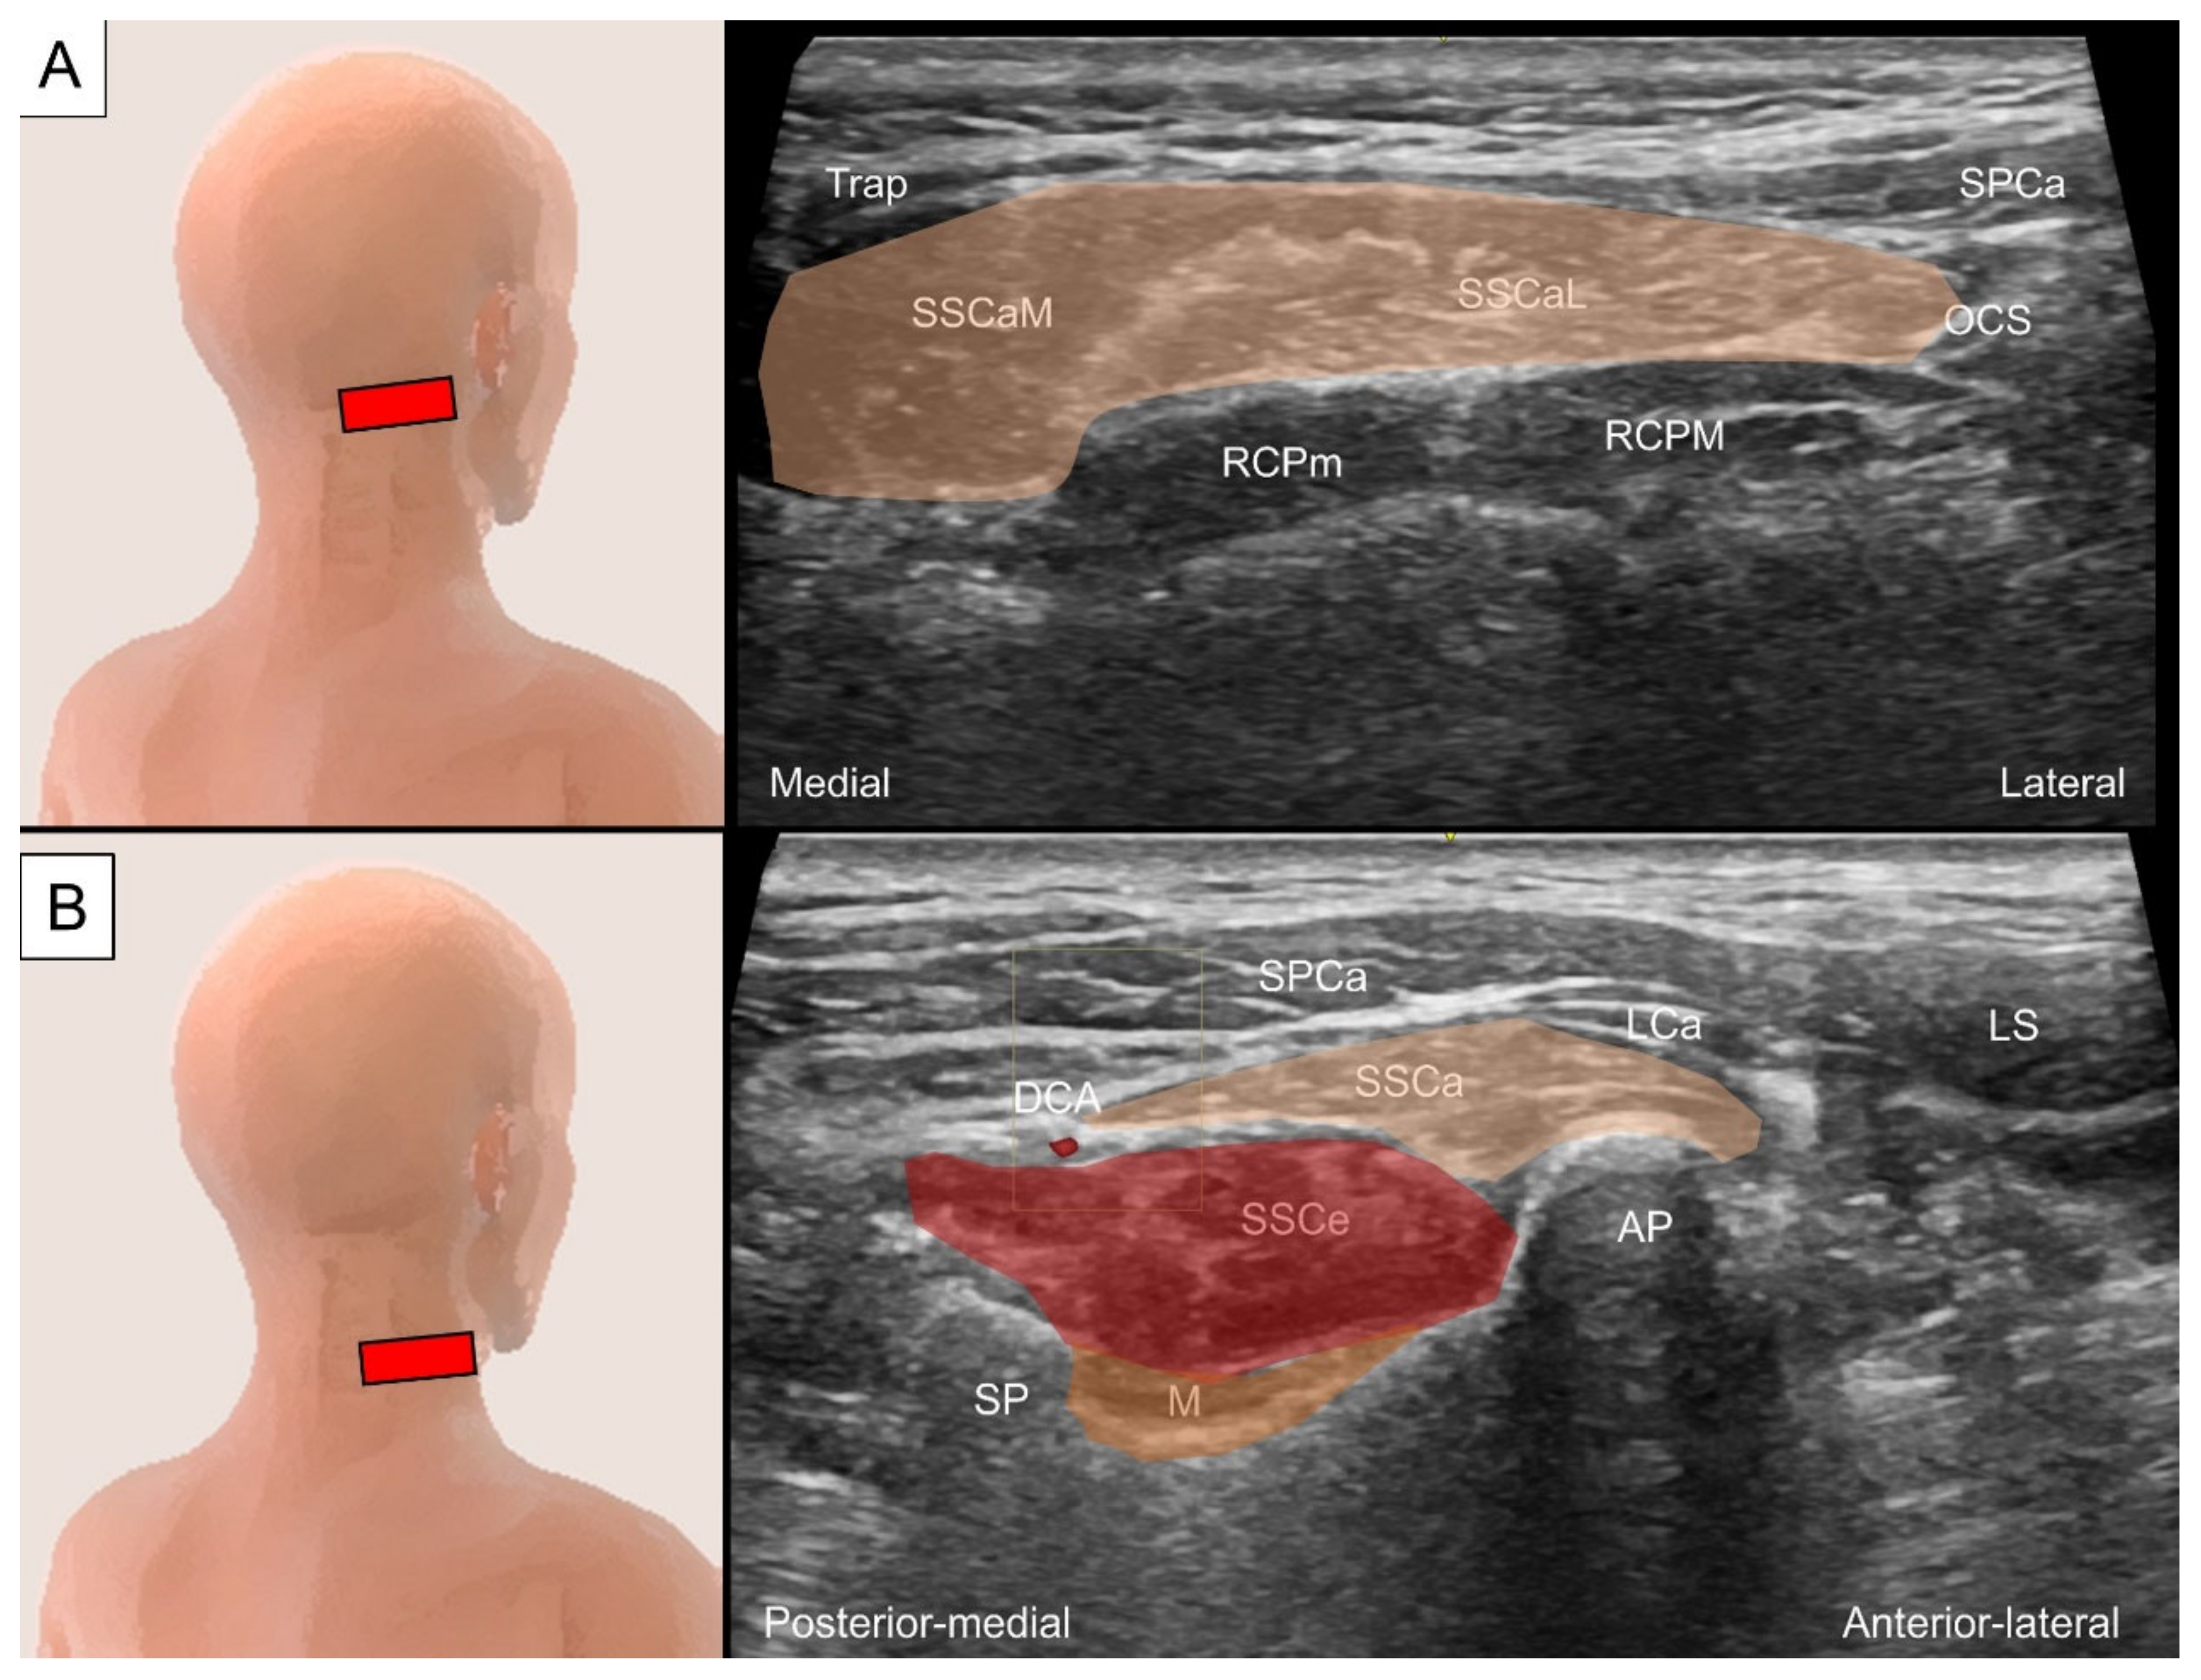

4.3.2. Sonographic Scanning

4.3.3. Clinical Relevance